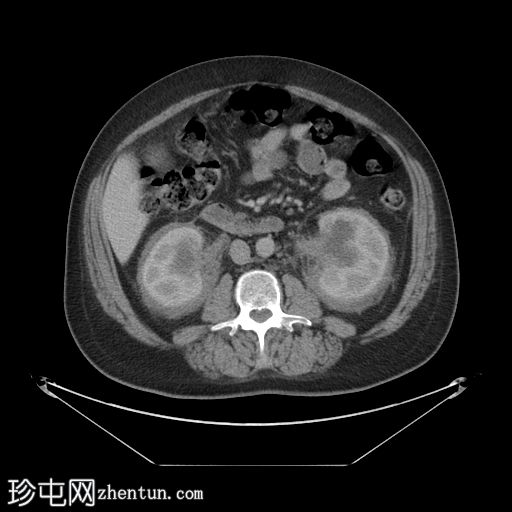

轴位增强扫描(门静脉期)

肾周可见重度、相对均匀的浸润,呈“毛肾征”。肾积水,但无输尿管积水。

肝、脾、胰腺和肾上腺正常。胆囊正常,无胆管扩张。